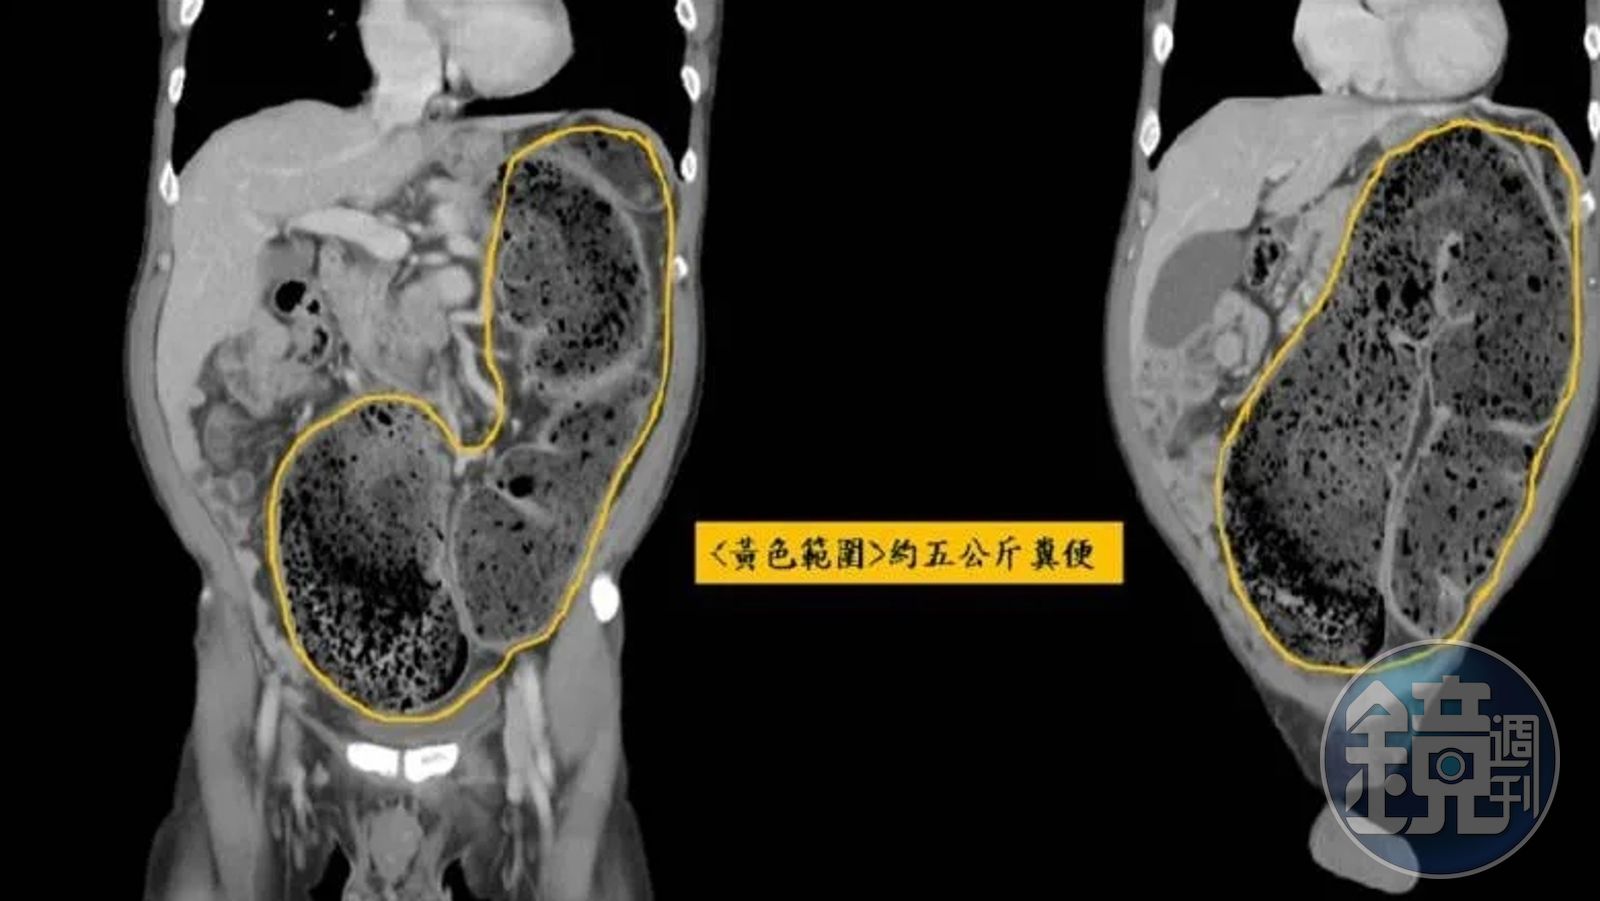

據了解,58歲男子經電腦斷層掃描,發現有異於常人約80公分的乙狀結腸,塞了約5公斤的宿便,一路頂到橫膈膜、胸腔,甚至還頂到心臟。大腸直腸外科醫師張巨成透露,該男子當時約有6*6公分的糞石,堵在大腸和乙狀結腸交接的地方,因此只能透過手指將糞石捏碎,花了約10分鐘將大糞石慢慢挖出來,而男子症狀也得到了緩解,回家排了十幾次便後,才將20天約5公斤的宿便排出。